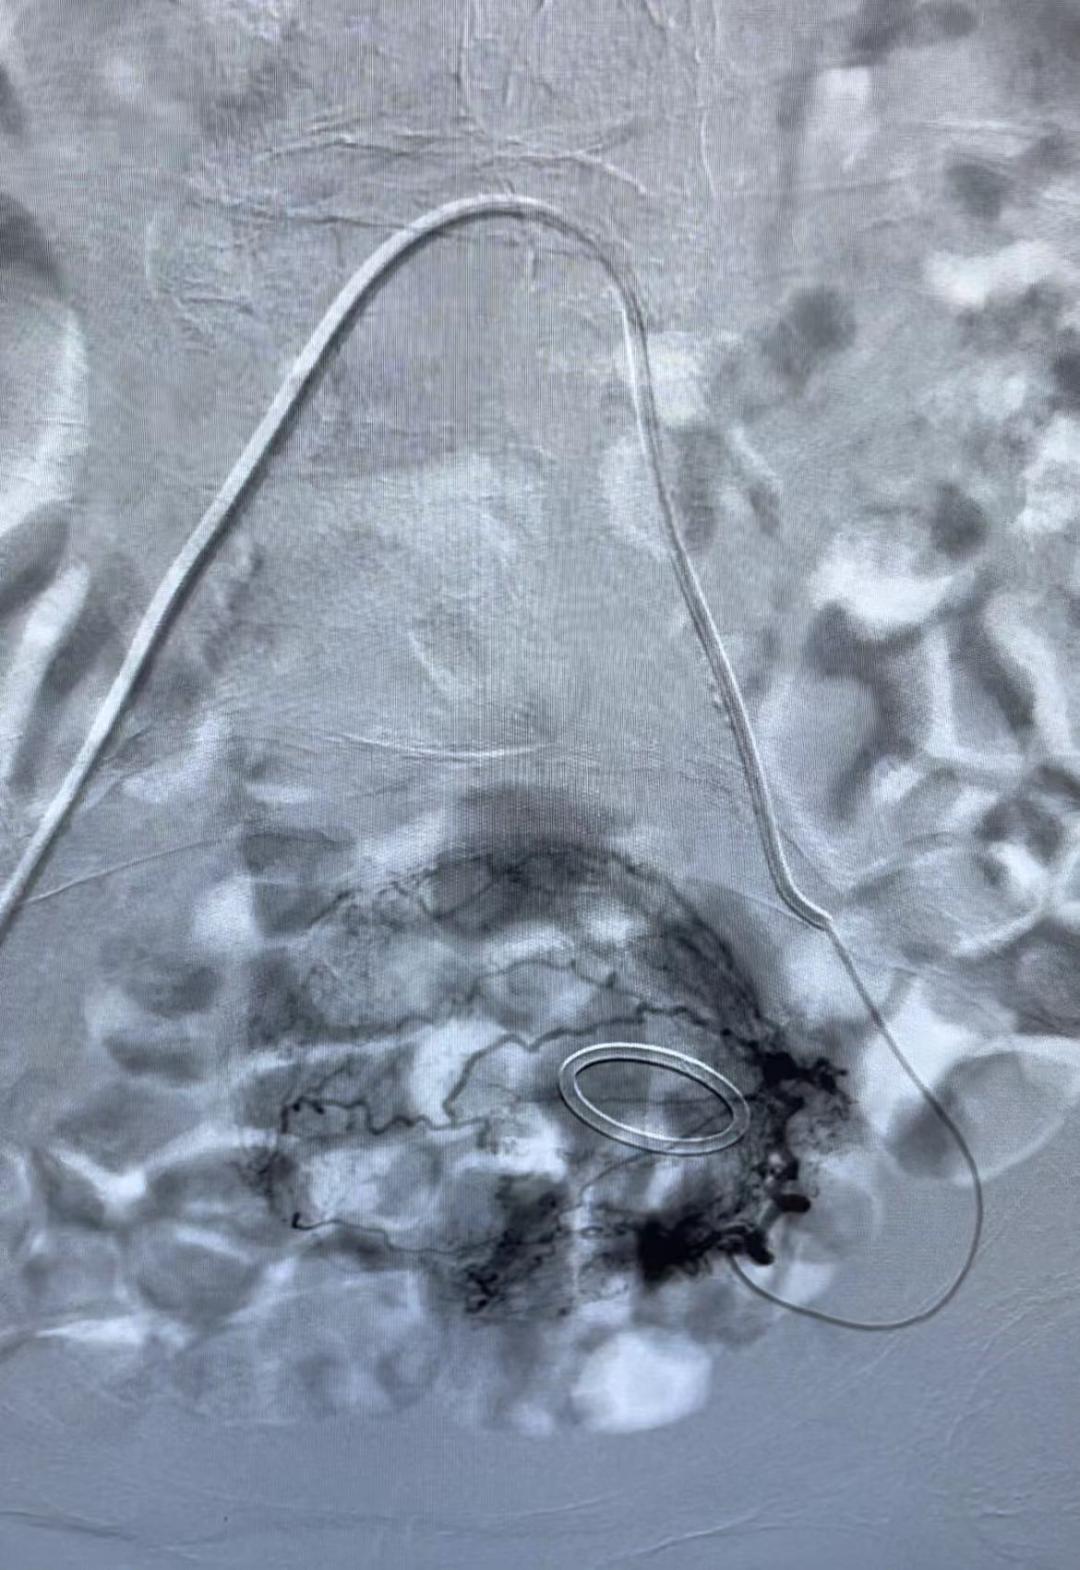

通过阴道填塞止血、药物止血,出血的问题解决得都不理想,肿瘤科马上参与到救治中来,肿瘤科鲍新医生会诊后评估,认为患者阴道流血时间长,同时,短期出血量进行性的增多引起了贫血并加重,考虑宫颈癌合并活动性出血,有大出血危及生命风险,有血管介入治疗止血指征,李岩与鲍新两位医生立即给患者施行了左右子宫动脉灌注化疗栓塞术,历时1小时,手术顺利完成。手术后,患者阴道流血明显减少,头晕和乏力的症状也明显缓解,可以安排后续的放化治疗方案。

栓塞前和栓塞后造影对比

栓塞前造影剂外溢显影

栓塞后造影剂外溢明显减少